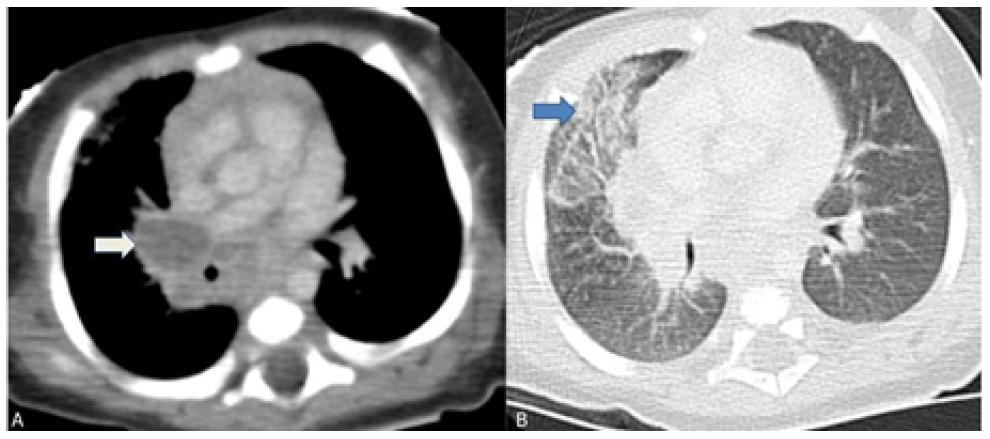

After reevaluation of the chest radiograph, which remained unchanged, a computed tomography (CT) scan of the chest showed multiple adenopathies in the middle mediastinum compressing the trachea, right main bronchus, and venous vascular structures, with ground-glass opacities in the anterior segment of the right upper lobe, in anatomic correlation with the airway obstruction (Figure 2).

Figure 2 Chest computed tomography scan showing multiple mediastinal adenopathies causing external airway compression. (A) Right hilar adenopathies compressing the right main bronchus (white arrow); (B) Ground glass opacity of the anterior segment of the right upper lobe indicating atelectasis (blue arrow).

Regarding pulmonary and thoracic imaging in children, chest radiography often shows opacity with minimal parenchymal involvement that correlates with the primary complex. However, airway obstruction (e.g., due to lymphadenopathy) may result in consolidation or segmental lesion, leading to the collapse of a lung segment or lobe in the setting of infiltrate and atelectasis, as illustrated in this case.13 The role of chest CT should also be emphasized, as it is a very useful tool in cases of clinical and radiologic discrepancy, accurately accessing mediastinal ganglia involvement and airway compression, and helping to exclude other pathologies.14 Despite being an invasive exam, bronchoscopy should be performed to better characterize airway compression and/or endobronchial lesions and when there is a high clinical suspicion despite negative microbiological results or when treatment response is inadequate.